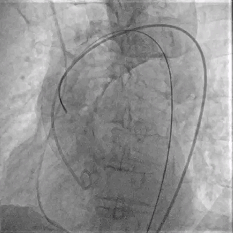

Step 4.输送系统进入:过弓性能优异,悬空通过,整体过程未将鞘管顶起至弓顶部

Step 5.瓣膜定位与释放:高起始位逐渐向下推送保持良好同轴性,无位移

Step 6.工作位观察:真实瓣环下方2mm,位置合适,决定释放,一次完成

Step 7.瓣膜脱钩:脱钩稳定无位移

Step 8.最终造影:真实瓣环下方3mm标准位,完全同轴,轻微反流,猪尾撤出后反流完全消失

过弓示意图